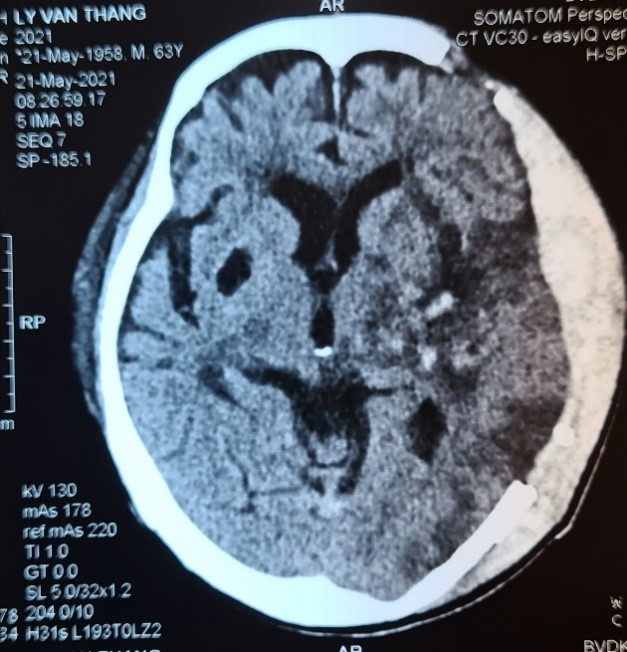

Hình ảnh chụp cắt lớp vi tính sọ não trước và sau phẫu thuật: Khối máu tụ được lấy hết hoàn toàn, nhu mô não được giải áp tốt, ít tổn thương